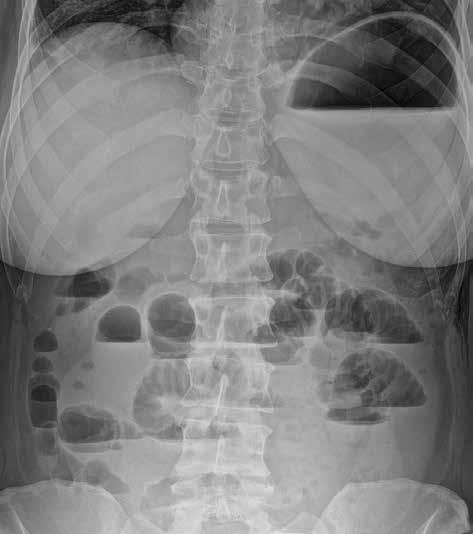

Volný vzduch v peritoneální dutině je většinou známkou patologické komunikace trávicí trubice s volnou dutinou břišní (obr. 4). Pravidelně ho vídáme po břišních operacích, zejména po laparoskopii. U prostého snímku břicha horizontálním paprskem je centrální paprsek zaměřen do středu spojnice hřebenů lopat kyčelních, a subdiafragmatický prostor je tak zobrazen zespodu šikmo, a ne tangenciálně. Výsledkem je superpozice s masou celých jater a sumace především s dorzálním diafragmatickým recesem, vyplněným vzdušnou plicní tkání. Větší diagnostický význam při detekci plynu pod bránicí má proto prostý snímek hrudníku vestoje. Volný plyn je detekovatelný i na snímku břicha vleže na zádech (znamení dvojité stěny – „double wall“ sign) (obr. 5). Malé množství volného plynu v dutině břišní je však takto nezobrazitelné. Také srůsty mohou bránit migraci plynu do podbráničních prostor, a tím zvyšovat falešnou negativitu vyšetření. Nejčastějšími příčinami pneumoperitonea jsou perforace trávicí trubice (vředová choroba gastroduodenální, komplikovaná divertikulitida, traumatické či iatrogenní příčiny). Kromě trávicí trubice

Obr. 4: RTG snímek břicha vestoje. Pneumoperitoneum. Srpovité projasnění volného plynu pod pravou brániční kopulí.